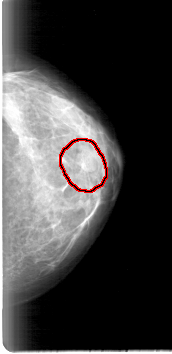

D_4000_1.LEFT_CC

LEFT_CC LINES 5296 PIXELS_PER_LINE 2566 BITS_PER_PIXEL 12 RESOLUTION 43.5 OVERLAY

FILE: D_4000_1.LEFT_CC.OVERLAY

TOTAL_ABNORMALITIES 1

ABNORMALITY 1

LESION_TYPE MASS SHAPE LOBULATED MARGINS CIRCUMSCRIBED

ASSESSMENT 0

SUBTLETY 4

PATHOLOGY BENIGN

TOTAL_OUTLINES 1

BOUNDARY